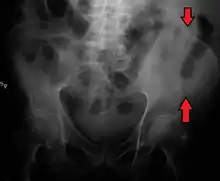

Clinical significance

A fracture of the left iliac wing